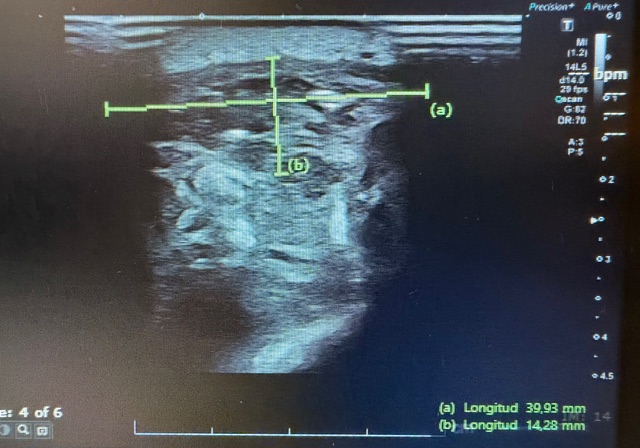

Hallazgos ecográficos

La ecografía muestra una lesión sólida hipoecoica, heterogénea y de contornos irregulares, situada entre la musculatura gemelar lateral y la musculatura peronea, con tamaño aproximado de 2,6–3,2 cm. Presenta áreas anecoicas compatibles con degeneración quística, pequeños focos hiperecogénicos sugestivos de calcificaciones y engrosamiento fascial con pérdida de la arquitectura normal. El estudio Doppler identifica vascularización interna arterial y venosa. Los hallazgos son compatibles con lesión mesenquimal profunda y potencialmente agresiva.